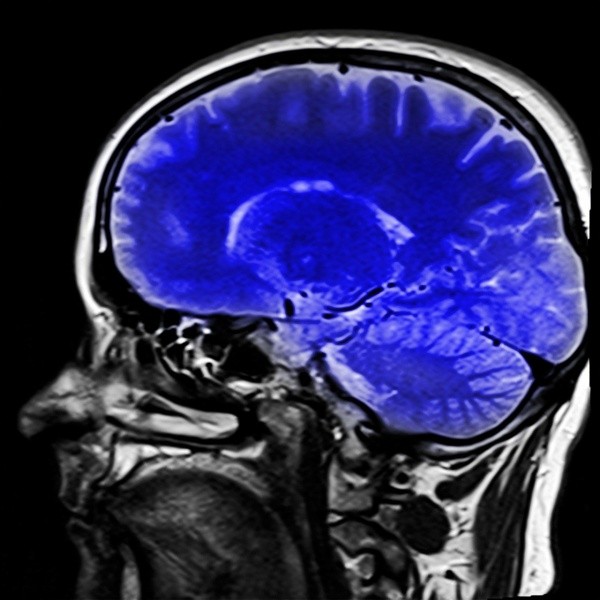

В реестр данных вошли 124 тысячи МРТ-снимков от сотни тысяч людей самого разного возраста, начиная с 16-недельного эмбриона и заканчивая человеком, который отметил вековой юбилей. Как говорят эксперты, потребовался почти петабайт данных.

Свою базу Brain Charts авторы выложили в свободном доступе для своих коллег-ученых по всему миру, которые заняты изучением мозга человека и, в частности, его возрастных изменений. Так, с его помощью можно оценить, как меняется доля белого и серого вещества со временем.